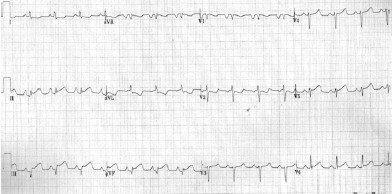

Colega quer transferir às 3 horas da manhã, do hospital de Viamão, paciente com 72 anos atendido na Emergência, apresentando dor retroesternal há duas horas. Relata que o paciente está com PA 110/70mmHg e sudorético. A ausculta cardíaca na fúrcula esternal (Fig. A), o Rx de tórax (Fig. B) e o eletrocardiograma (Fig. C), transmitidos via eletrônica, estão representados abaixo.

Fig. C